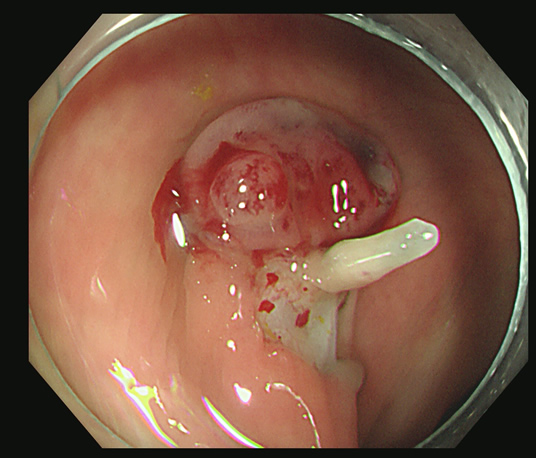

これをカンシで大きくつかみ取ります

これで、初めて完全切除と判断されます